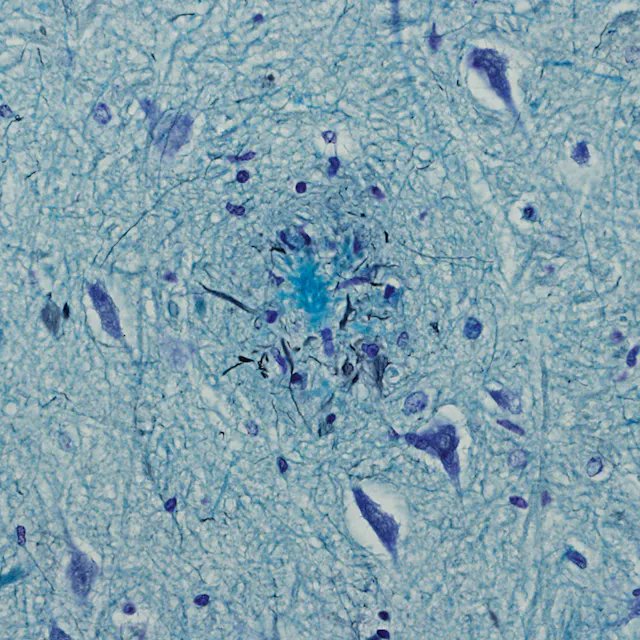

Years can pass before dementia is diagnosed, also because not every blackout is a sign of memory loss. The causes of dementia remain unclear and there is no cure for it as yet.

“Detecting dementia in its early stages is virtually impossible for the layman,” explains Hansjoerg Ledermann, chief physician at the Adullam. On the one hand, this is because the early symptoms of the disease do not differ markedly from normal behavior. On the other hand, almost 10 years can elapse between the actual outbreak of the disease and the time when the first symptoms appear – thus making early diagnosis even more difficult.

For this reason, all patients admitted to the Adullam undergo various routine dementia examinations, including brain scans and classic memory tests.

“If detected early enough, progression of the disease can be delayed with medication even if it cannot be cured. The goal of geriatric medicine is to ensure that patients can experience a period of prolonged health,” explains Ledermann.

In patients with a mild form of dementia, anti-dementia drugs such as the Novartis medication Exelon® can help to slow the progression of the disease. Patients are also given ginkgo supplements and other substances which can promote brain performance.